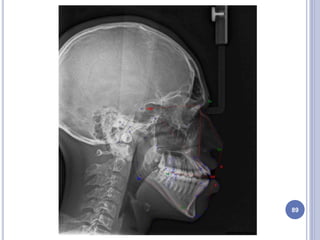

PRE-SURGICAL DATABASE

 Primary components of the pre surgical database are the

clinical examination, lateral and anteroposterior cephalometric

radiographs, and the articulator-mounted models.

 Secondary components are panoramic and periapical

radiographs and facial and intraoral photographs.

 Functional problems related to the patient -

Temporomandibular joints and malocclusion are recorded.

 In the frontal plane, the clinician establishes, a clinical midline

and integrates diagnostic information in relation to that

reference line. Upper lip support is an important clinical

feature. An assessment of upper lip support will provide the

clinician with information regarding the proper antero-posterior

position of maxilla relative to facial soft tissues. 50